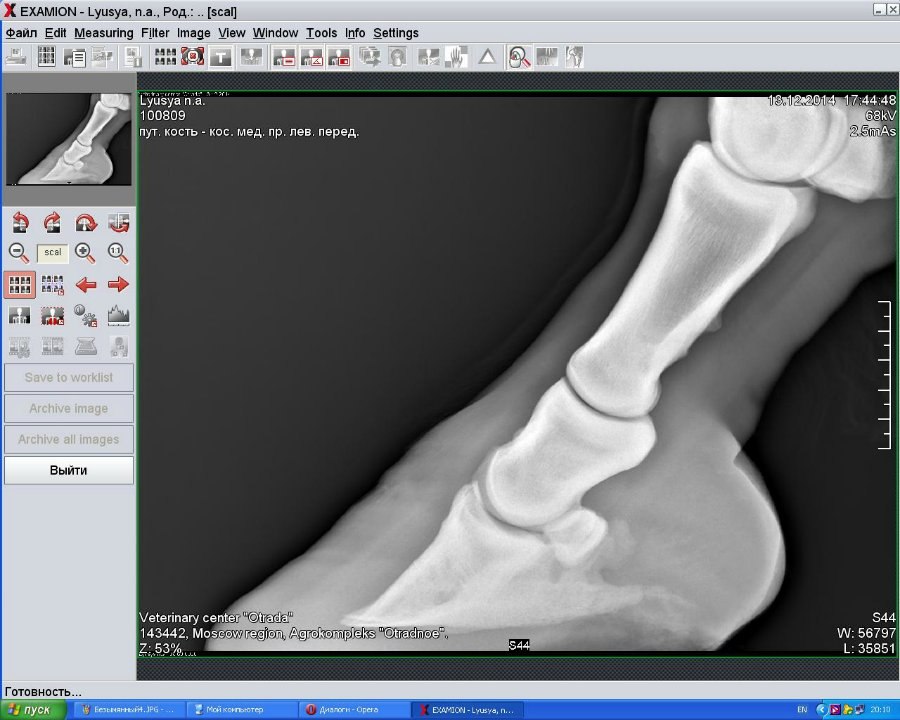

Левый перед (2014)